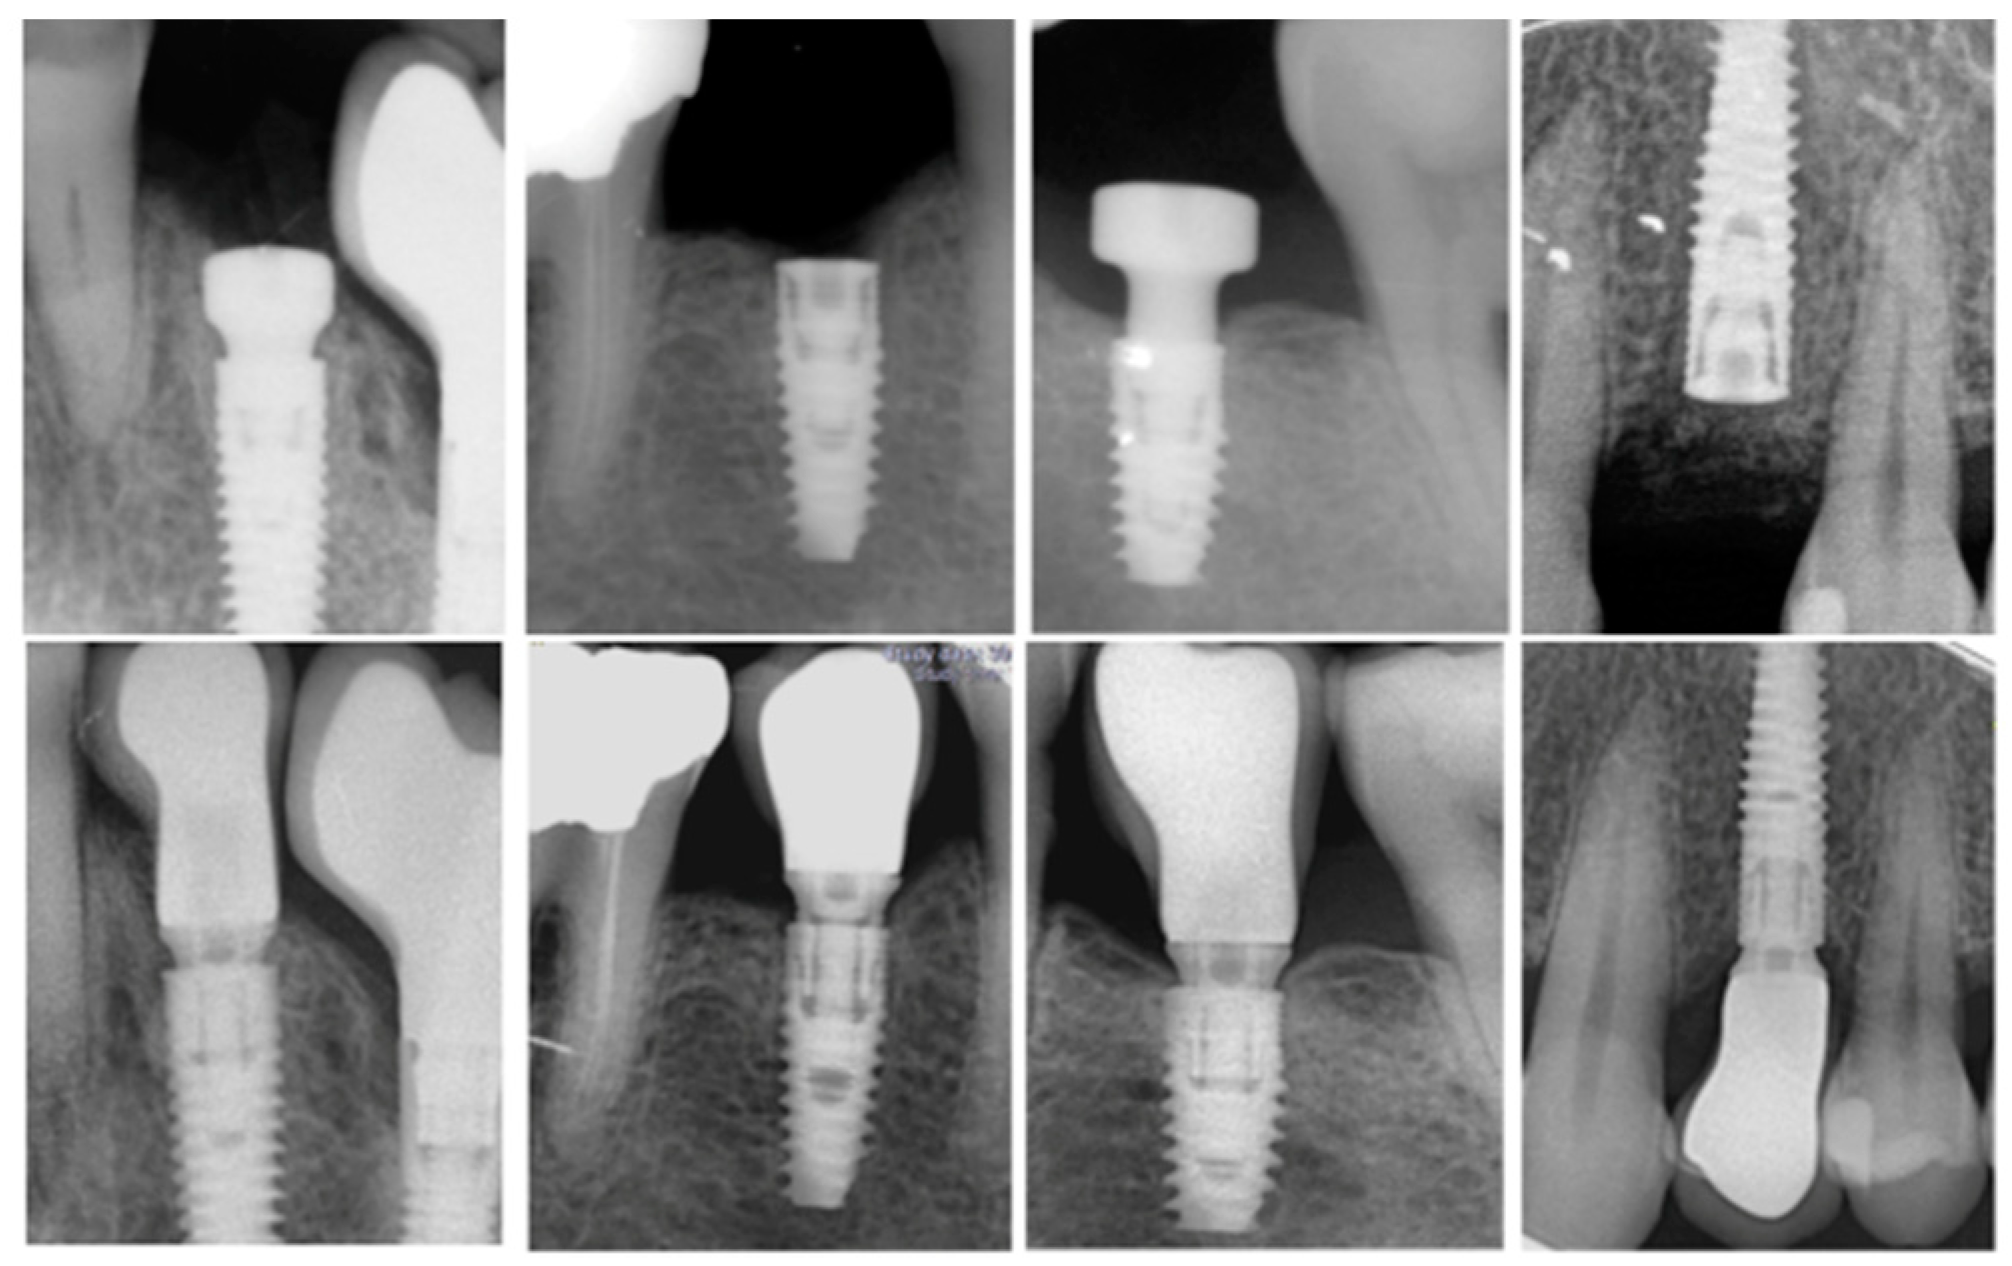

Failed Dental Implant X Ray .   dental implant failure is classified as early and late implant failure.  in this article, we address various aspects of ailing and failed dental implants: Implant survival, diagnosis, criteria for initiating.   despite the high success rates and stability of dental implants, failures do occur. Early implant failure means an implant. While surgical trauma together with bone volume and. Implant survival, diagnosis, criteria for initiating implant removal, explantation.   early detection and treatment of initial progressive bone loss around dental implants by mechanical debridement with.   mechanical failures in dental implants can result from a combination of factors, including material fatigue [ 5 ],.

in this article, we address various aspects of ailing and failed dental implants: Implant survival, diagnosis, criteria for initiating.   early detection and treatment of initial progressive bone loss around dental implants by mechanical debridement with. While surgical trauma together with bone volume and.   dental implant failure is classified as early and late implant failure.   despite the high success rates and stability of dental implants, failures do occur. Implant survival, diagnosis, criteria for initiating implant removal, explantation. Early implant failure means an implant.   mechanical failures in dental implants can result from a combination of factors, including material fatigue [ 5 ],.

Failed Dental Implant X Ray    mechanical failures in dental implants can result from a combination of factors, including material fatigue [ 5 ],. Implant survival, diagnosis, criteria for initiating implant removal, explantation.   mechanical failures in dental implants can result from a combination of factors, including material fatigue [ 5 ],.  in this article, we address various aspects of ailing and failed dental implants: While surgical trauma together with bone volume and.   early detection and treatment of initial progressive bone loss around dental implants by mechanical debridement with. Implant survival, diagnosis, criteria for initiating. Early implant failure means an implant.   despite the high success rates and stability of dental implants, failures do occur.   dental implant failure is classified as early and late implant failure.